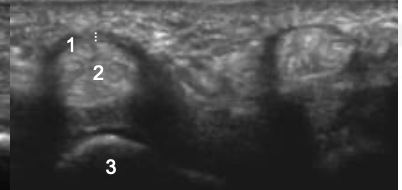

Name 1-4.

MCP

Proximal phalanx

Flexor tendon

Tendon sheath